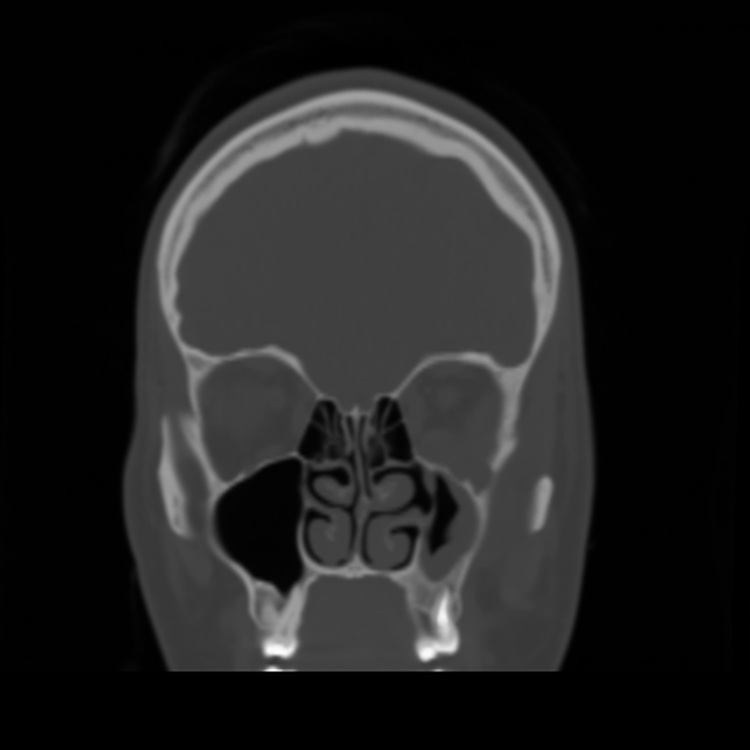

#AJNRcc >> November 20, 2025 >> What is the diagnosis for this 22-year-old woman with an insidious onset of diplopia, left ophthalmoparesis, trismus, and a history of root canal treatment with persistent left facial pain for 2 years. Submit your answer at https://t.co/L2j0hK0RCd.